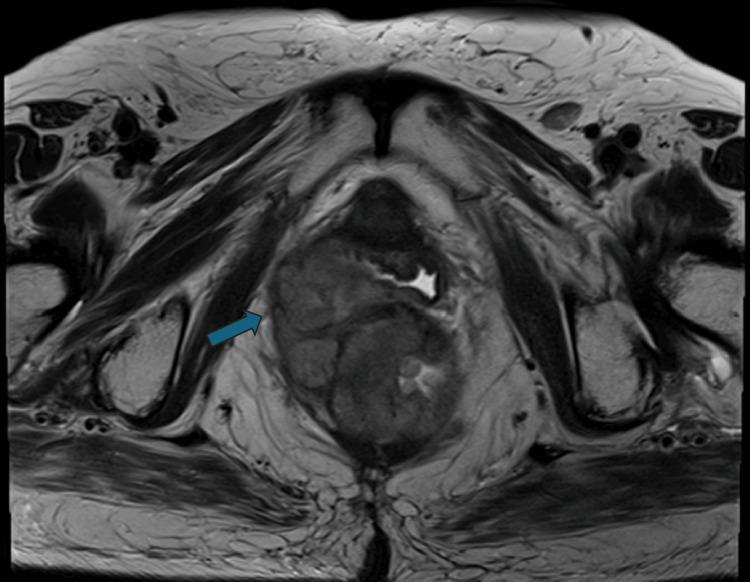

Anorectal melanoma (ARM) is a rare entity with aggressive biological behavior and poor prognosis. Clinically, ARM presents with atypical symptoms, such as anal pain and bleeding, thus often being misdiagnosed as a benign anorectal pathology and leading to delayed diagnosis. We present a case of a 73-year-old female patient with stage I ARM, treated successfully with a combination of neoadjuvant-adjuvant immunotherapy (nivolumab, an anti-PD-1 monoclonal antibody) and abdominoperineal resection. The patient is disease-free at a five-year follow-up after the operation, suggesting that long-term targeted immunotherapy offers a durable and promising response. This case highlights the critical role of a multidisciplinary approach, involving specialists in ARM surgery and systemic therapies, to improve prognosis and ensure an optimal quality of life for patients with ARM. Given the limited scientific evidence, further prospective and randomized trials are required to develop effective systemic therapies and improve the survival of patients with ARM.

摘要

肛管黑色素瘤(ARM)是一种罕见的疾病,具有侵袭性生物学行为且预后较差。临床上,ARM表现为非典型症状,如肛门疼痛和出血,因此常被误诊为良性肛管病变,导致诊断延迟。我们报告一例73岁I期ARM女性患者,通过新辅助-辅助免疫治疗(纳武单抗,一种抗PD-1单克隆抗体)联合腹会阴切除术成功治疗。术后五年随访时患者无疾病,表明长期靶向免疫治疗可提供持久且有前景的反应。该病例突出了多学科方法的关键作用,包括ARM手术和全身治疗专家,以改善预后并确保ARM患者的最佳生活质量。鉴于科学证据有限,需要进一步进行前瞻性和随机试验,以开发有效的全身治疗方法并提高ARM患者的生存率。